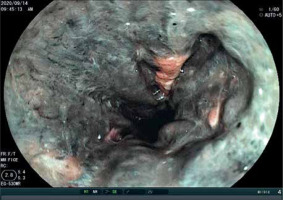

Endoscopy was performed in 176 patients with corrosive substance intake. The most severe endoscopy findings (high-grade injury) were significantly associated with acid and base ingestion in all 3 endoscopy sites (Table II; Figures 1–3).

Figure 2

Endoscopic finding of stomach in female after ingestion of hydrochloric acid ingestion (grade III)